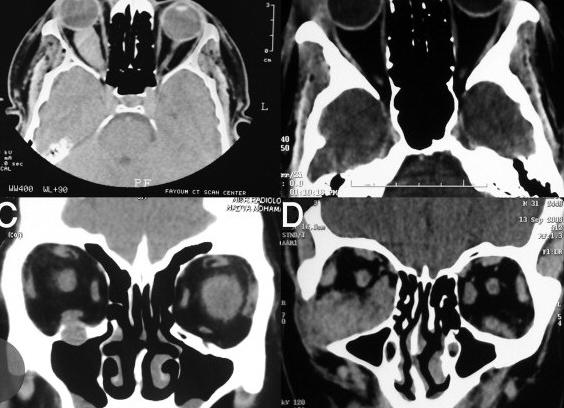

Расшифровка томографии осуществляется врачом-офтальмологом. На КТ можно диагностировать опухоль внутри орбиты или рядом с ней. При этом оценивают изменение контуров глазного яблока, деформацию зрительного нерва и костей глазницы, нарушения сетчатки. Каждый вид опухоли имеет свои особенности.

Раньше вид опухоли определяли только во время операции. Сейчас КТ позволяет определить вид новообразования в процессе диагностики. Это важно, чтобы выбрать метод лечения: препаратами, посредством операции или лазерной коррекцией.

При экзофтальме можно узнать причину патологии — повреждение стенки глазницы или новообразование. При травме или попадании инородного тела выясняют тяжесть повреждения и расположение тела, нужна ли операция. КТ с контрастом определяет кровообращение глазницы, нарушения зрительного нерва.

Интерпретация результатов

На КТ глазных орбит можно чётко увидеть объёмные образования, расположенные как внутриорбитально, так и в соседней части. При этом происходит оттеснение, смещение и изменение контуров самого глазного яблока, зрительного нерва, деформация костей глазницы, изменения сетчатки. Каждый вид опухоли имеет свои морфологические и гистологические характерные особенности. Ранее определить вид новообразования можно было только во время или после операции. С помощью КТ по ряду рентгенологических признаков удаётся предположить тип опухоли ещё на стадии диагностики. Это особенно важно при выборе тактики лечения – консервативное, оперативное, лазерная деструкция.

При экзофтальме появляется возможность выявить причину заболевания – разрушение стенки глазницы, интраорбитальное новообразование, опухоль околоносовой пазухи.

При травмах, инородных телах можно оценить степень и тяжесть повреждения, локализацию, необходимость оперативного лечения.

КТ с контрастом даёт возможность исследования кровоснабжения глазного яблока, зрительного нерва.